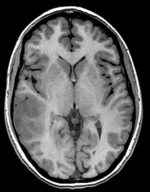

this is the fixed reference image. All images are aligned into this space lleft this is the T2 reference image, serves as target to the DTI baseline, but is itself aligned to the SPGR lleft this is the DTI tensor image, in the same orientation as the DTI Baseline

T1 SPGR

fixed image 1

This is a classic case of a multi-sequence MRI exam we wish to spatially align to the anatomical reference scan (T1-SPGR). The scan of interest is the DTI image to be aligned for surgical planning/reference. Unlike Case 27 this one does contain both a T1 and a T2 image. The T2 image being closer in contrast to the DWI/DTI baseline, it makes for the better registration reference. However the T1 contains the tissue contrast of interest.